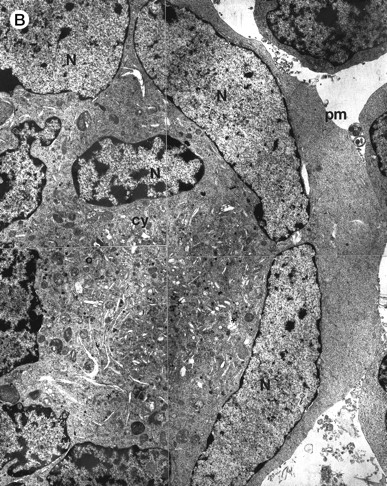

Morphologic examination of syncytia in HHV-7–infected SupT1 cultures (8 day pi) by light (A) and electron (B through E) microscopy. (A) Field with three syncytia and various single cells. (B) Multinucleated syncytium with an intact morphology. (C) Particular of a necrotic syncytium with vacuolized cytoplasm and initial discontinuation of the plasma membrane. Also note the lack of nuclear chromatin condensation. In (B) and (C), virions appear as dark points (asterisks). (D) Ringed nucleocapsids with an electron-dense core in the cytoplasm of a necrotic syncytium. (E) Particular of a syncytium in advanced stage of necrosis (bottom left), releasing mature virions (asterisks) in proximity of an intact cell (top right). N, nucleus; cy, cytoplasm; v, vacuole; pm, plasma membrane. Original magnifications: (A) ×400; (B and C) ×6,000; (D) ×36,000; and (E) ×7,000.

At ultrastructural examination, a significant fraction of syncytia still maintained an intact appearance with little loss of cytoplasmic and nuclear organization despite the presence of numerous virions in the cytoplasmic compartment (Fig 2B). Although cytoplasmic virions were also observed in single cells, all syncytia invariably contained large amounts of typical herpesvirus nucleocapsids, which appear as single, ringed particles with an electron-dense center representing the core.27 28

However, most syncytia exhibited a vacuolized cytoplasm and discontinuation of the plasma membrane with lack of chromatin condensation, which are considered typical ultrastructural features of necrosis (Fig 2C). The morphologic features of necrosis were always associated with the presence of nucleocapsids in the cytoplasm (Fig 2D) and often with the release of mature virions in the extracellular space (Fig 2E). To ascertain that the ultrastructural features of syncytia shown above were truly representative of HHV-7 infection, various syncytia obtained from two separate experiments were analyzed. The presence of large amounts of cytoplasmic virions was confirmed in all syncytia examined, strongly suggesting that these giant multinucleated cells represented the major source of viral particles in the culture. Moreover, the majority of syncytia showed morphologic evidences of necrosis, whereas less than 5% showed apoptotic features (Table 1).